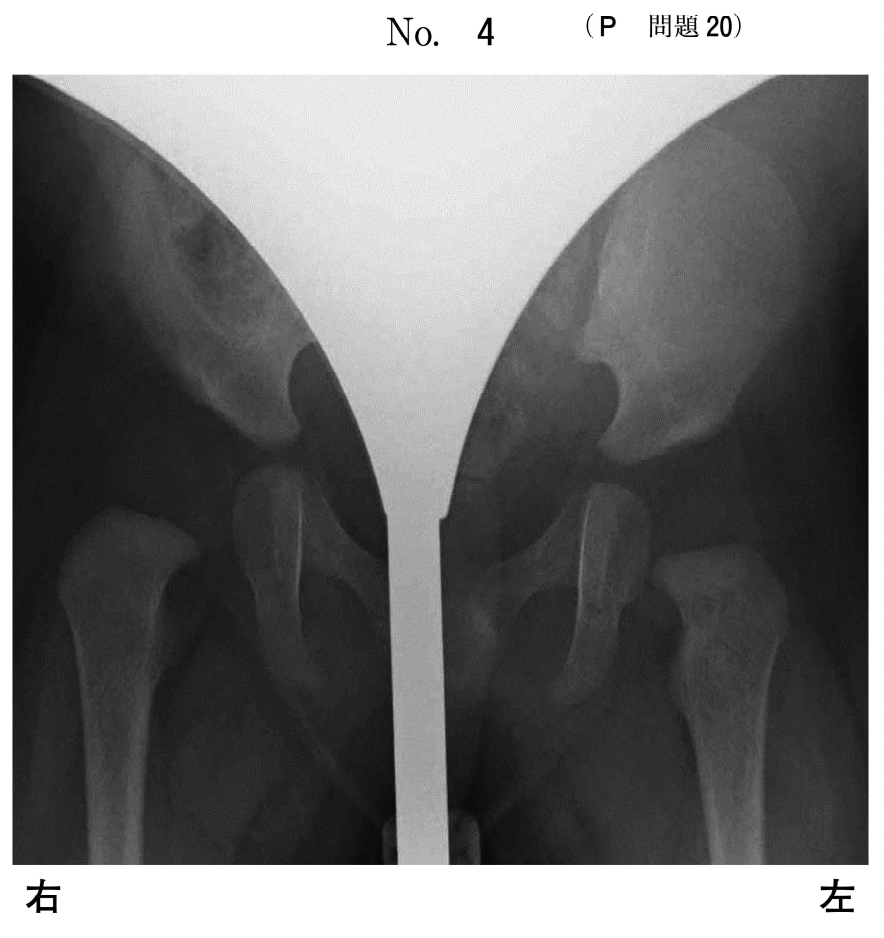

生後4か月の乳児。健診で股関節の異常を指摘された。来院時に右股関節の開排制限を認めたため、股関節の工ックス線単純検査を行った。

この患児の股関節の工ックス線単純写真(別冊No.4)を別に示す。行うべき対応として適切なのはどれか。